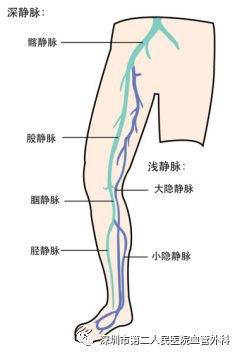

深静脉血栓形成的英文简称叫DVT,多发生于下肢,可发生于髂静脉、股静脉、腘静脉、胫静脉及小腿肌肉静脉丛等各级深静脉(图1)。此病在中老年朋友中并不少见,特别是有血栓形成高危因素的人群中更是多见。那么,静脉血栓因何产生?为什么好发于下肢深静脉?如何发展?有何危害?遇到这种情况,我们又该如何应对呢?

图1 下肢各级深静脉及其与浅静脉的关系